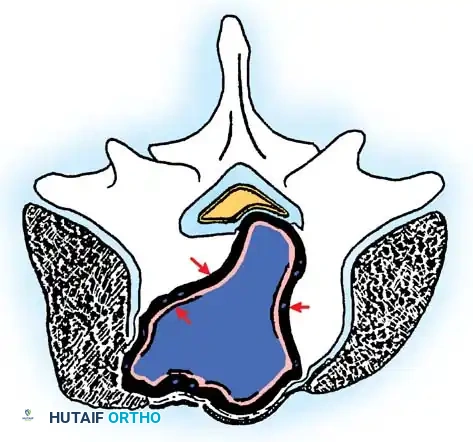

Fig. 41-30: Enneking staging of benign spinal tumors. Capsule of tumor is indicated by 1, and reactive pseudocapsule is indicated by 2. Stage 3 aggressive benign tumors can expand through the posterior vertebral wall and compress the cord. The pseudocapsule is vascularized reactive tissue and can adhere to the dura.

Stage 3: Aggressive Tumors

Despite being histologically benign, Stage 3 lesions (e.g., giant cell tumors, aggressive osteoblastomas) are locally destructive. They breach the tumor capsule, invade local compartments, and have a high propensity for recurrence.

Cross-sectional view of a Stage 3 aggressive benign tumor breaching the posterior vertebral wall, highlighting the necessity for wide excision to prevent local recurrence.

Wide excision—removal of the tumor with a continuous cuff of normal, healthy tissue—is the oncologic treatment of choice. A marginal excision (dissecting through the reactive pseudocapsule) leaves microscopic disease and results in unacceptably high recurrence rates.